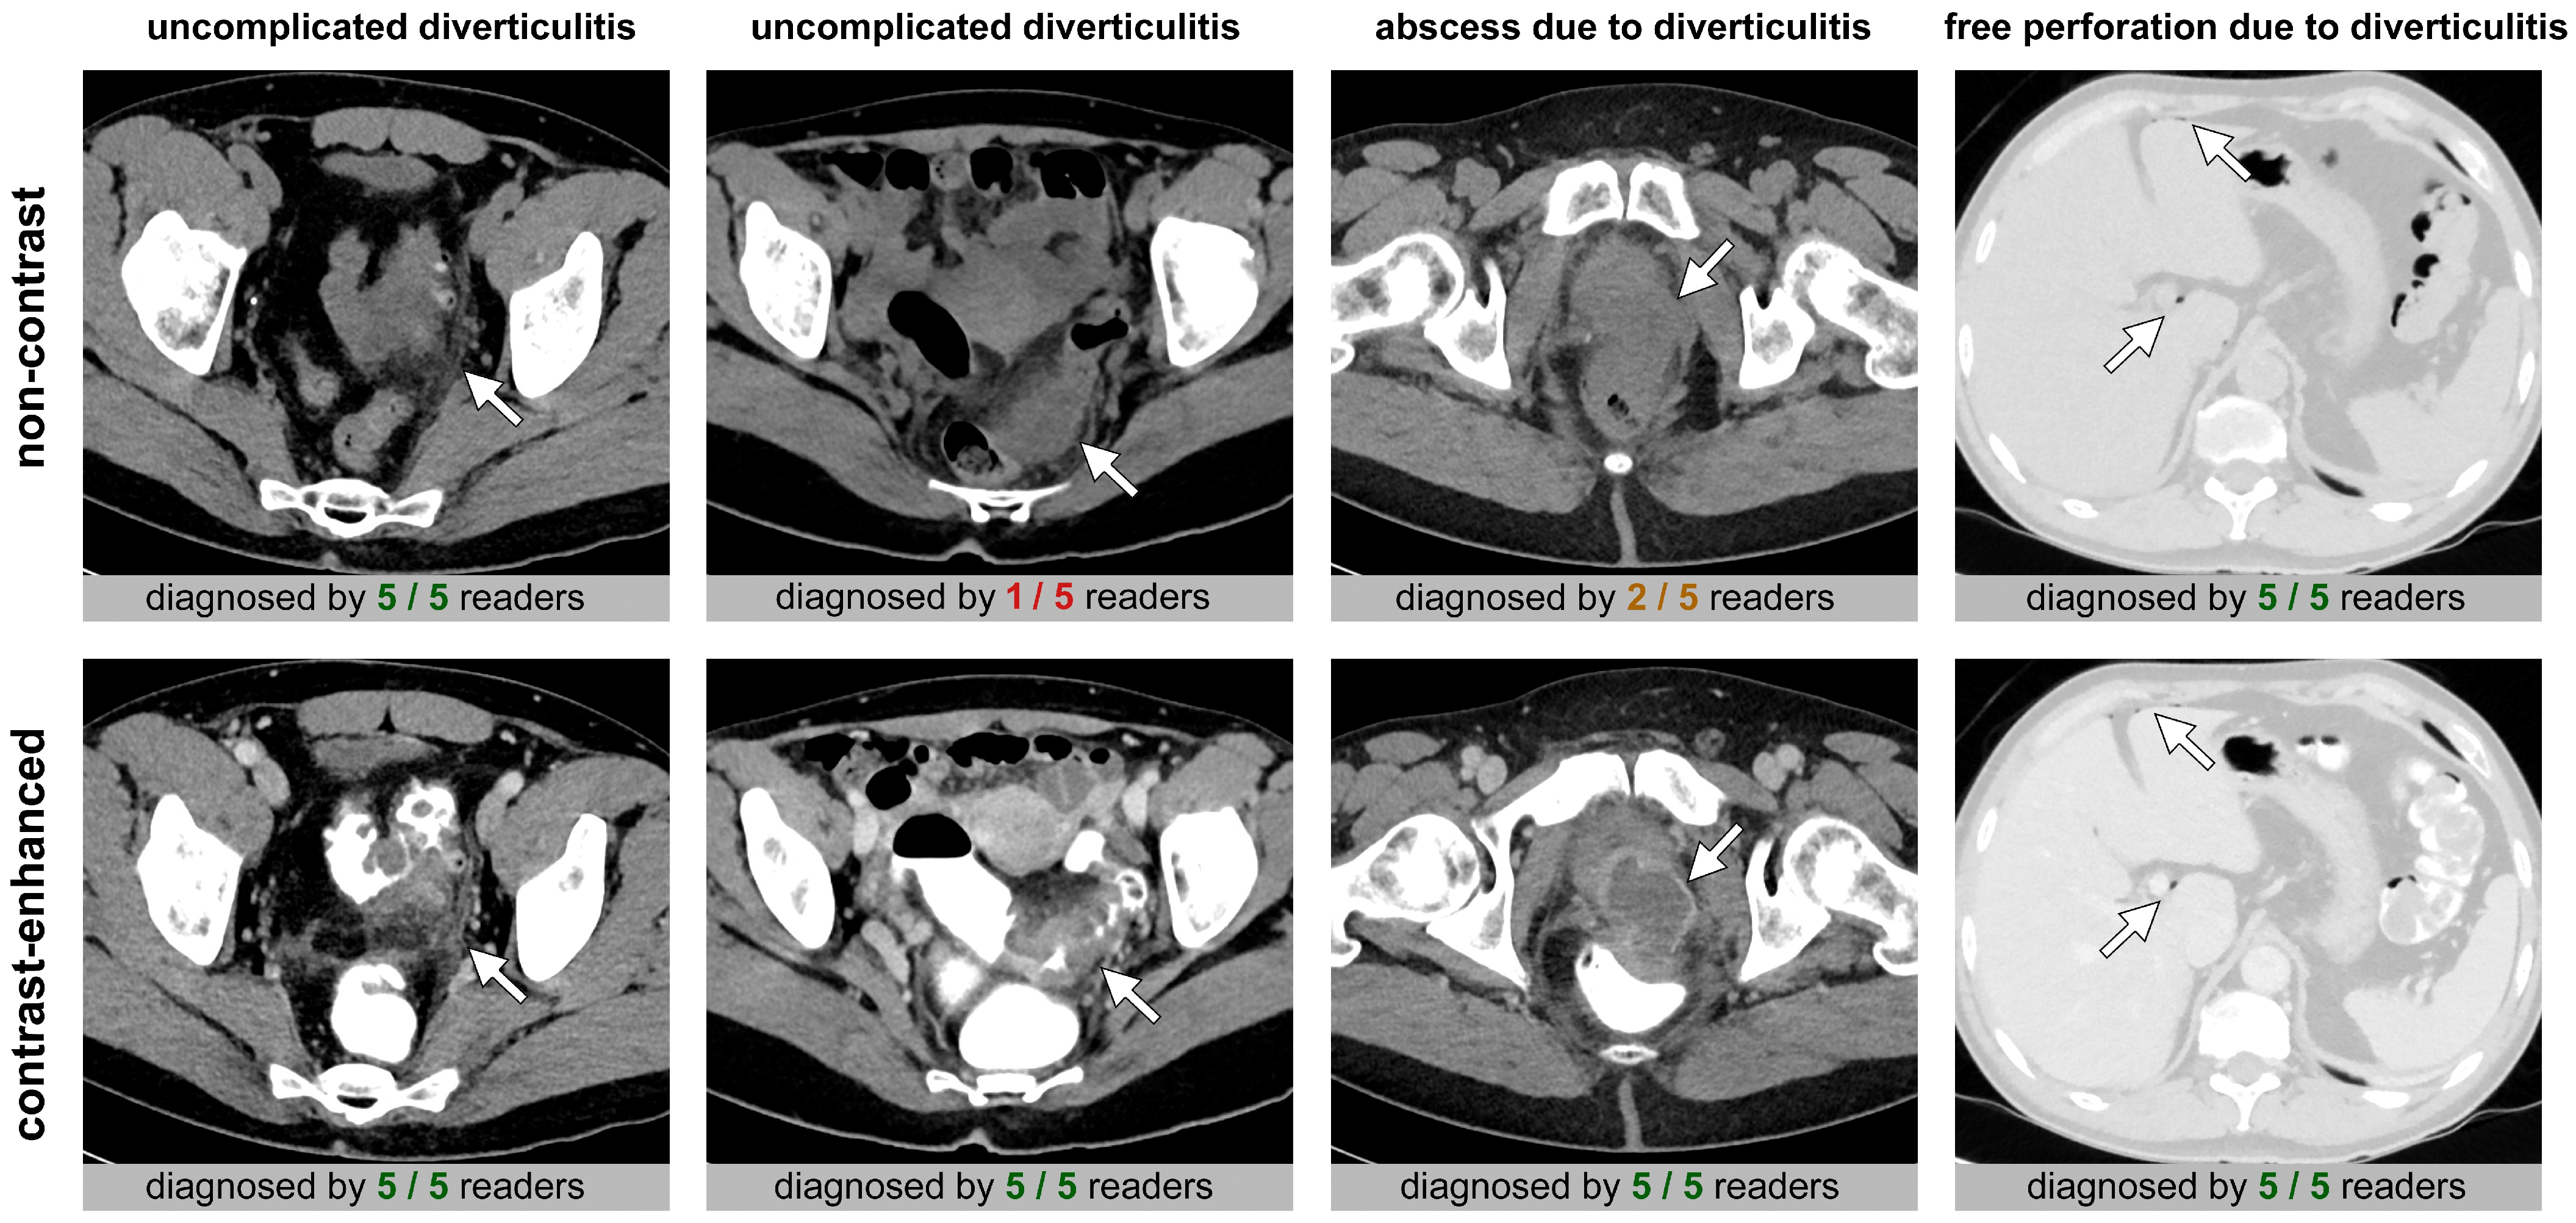

3.1. Diagnosis of Diverticulitis, Perforation, and Abscess—Radiologists’ Diagnostic Performance and Interrater Agreement